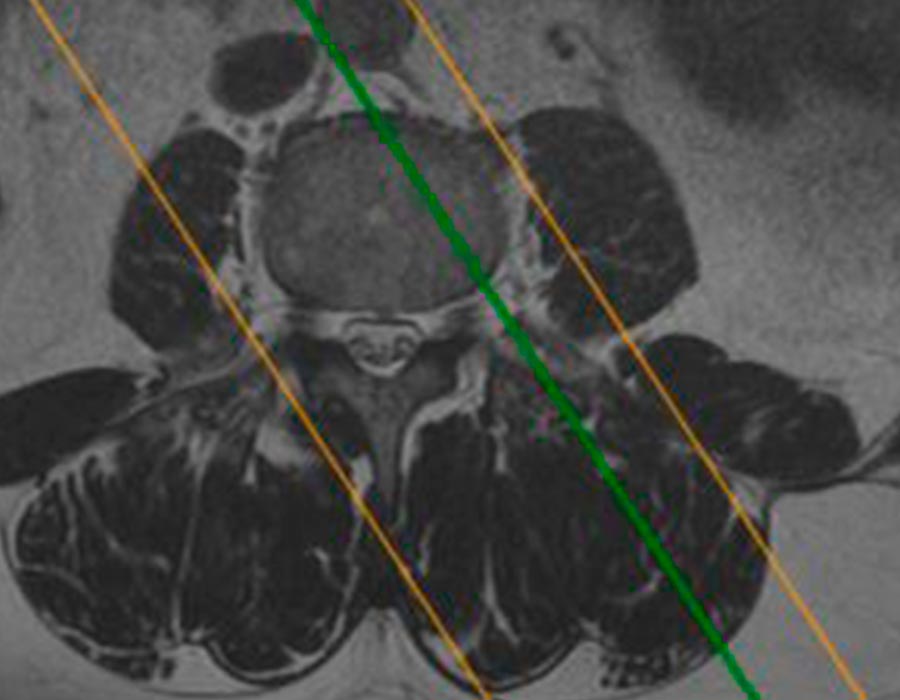

Cirugia endoscopia de columna